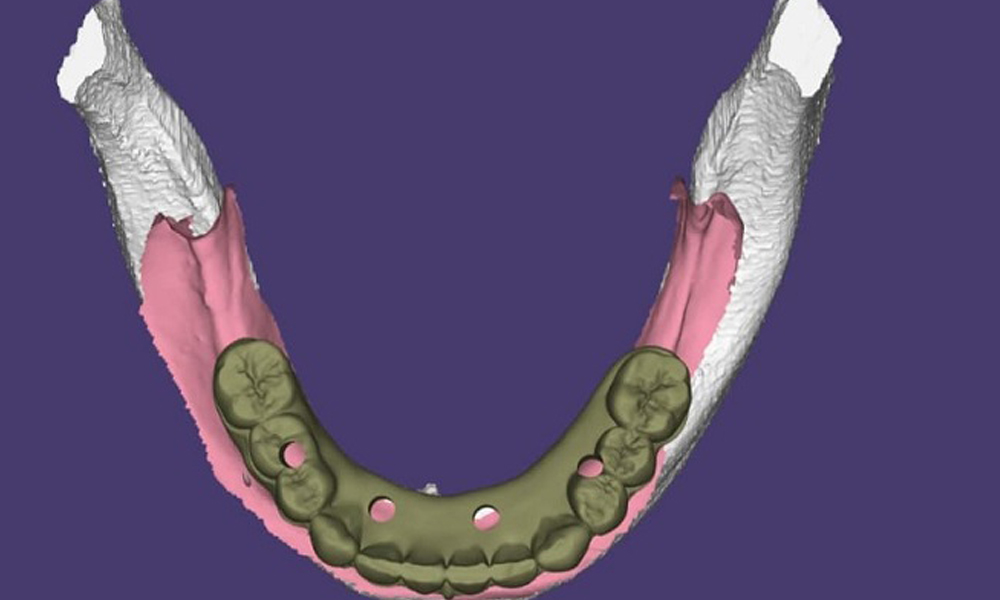

پس از گفتگوی اولیه، نوبت به ارزیابی بالینی و تصویربرداری تشخیصی میرسد. پزشک با دقت دهان، دندانهای باقیمانده، سلامت لثه و فضای مورد نظر برای ایمپلنت را معاینه میکند. در بسیاری از کلینیکهای مجهز تهران، یک عکس رادیوگرافی ساده (پانوراما) نیز در همان جلسه و به صورت رایگان گرفته میشود تا وضعیت استخوان فک، ریشه دندانهای مجاور و ساختارهای حیاتی به وضوح دیده شود. پس از گردآوری این اطلاعات کلیدی، پزشک تمام یافتهها، گزینههای درمانی، مراحل دقیق، زمانبندی، برندهای پیشنهادی و یک برآورد هزینه شفاف را به زبان ساده برای شما توضیح میدهد. اینجاست که شما میتوانید همه سوالات خود را بپرسید. مرحله نهایی، جمعبندی و ارائه برنامه درمانی مکتوب است و پس از آن، بدون هیچگونه تعهدی، میتوانید با آرامش در مورد ادامه کار تصمیم بگیرید. این ساختار منسجم، تضمین میکند که هیچ نکتهای در تاریکی نمانده و شما با چشمی باز وارد فرآیند درمان شوید.

۲. تصویربرداری تشخیصی اولیه | – عکس رادیوگرافی ساده (پانوراما یا OPG): در اکثر مراکز معتبر، به صورت رایگان گرفته میشود. این عکس نمای کلی از استخوان فک، موقعیت دندانها، سینوسها و عصبها ارائه میدهد. | ارزیابی اولیه از کمیت و کیفیت استخوان فک، شناسایی نیاز احتمالی به پیوند استخوان یا سینوس لیفت. |

۳. تصویربرداری رایگان و تفسیر حرفهای (اغلب پانوراما)

- در اکثر کلینیکهای مجهز، یک عکس رادیوگرافی پانورامابه صورت رایگان گرفته میشود.

- پزشک این عکس را مانند یک نقشه راه برای شما تحلیل میکند.

- کیفیت، تراکم و ارتفاع استخوان فک به وضوح ارزیابی میشود.

- موقعیت اعصاب مهم و سینوسها مشخص میگردد.

- هدف: ارزیابی علمی و دقیق از زیرساخت استخوانی و پیشبینی نیاز به اقدامات تکمیلی مثل پیوند استخوان.